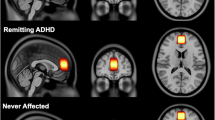

In order to determine brain activation differences between groups, we studied the MSIT-effect (InC > CC) for ADHD and TD children. For cluster detection threshold, we used a z value of 2.3; and, for cluster correction threshold, p < 0.05. In our task and MRI configuration, this setting has an adequate rate of false positive results (0.049, see Methods and Supplementary Material). Neuroimaging results showed a greater activation of the right medial and inferior frontal gyrus for the ADHD group (Fig. 3). Peaks of activity for this cluster are shown in Table 2.

Group differences elicited by MSIT-effect (ADHD[InC-CC] > TD[InC-CC] children).

When we compared the brain activation patterns elicited by the MSIT-effect between ADHD and TD groups, differences were significant only for the ADHD > TD contrast (Fig. 3). These differences were placed in a cluster with the activity peak located in the rlPFC. Thus, this over-activation could be interpreted in terms of a cortical compensatory mechanism in order to maintain an adequate performance during the task. Previous works have shown how cortical compensatory activity is a natural and relievable brain mechanism to cope with deficits in several cognitive processes, like response inhibition in ADHD35, 51,52,53, diffuse axonal injury54, multiple sclerosis55, 56 and schizophrenia57. The structural maturation delay of the dlPFC has also been related to persistent inattention symptoms in adults18. Thus, this functional alteration could be a marker of symptoms in adults, and can be related to other problems such as social anxiety disorder4.